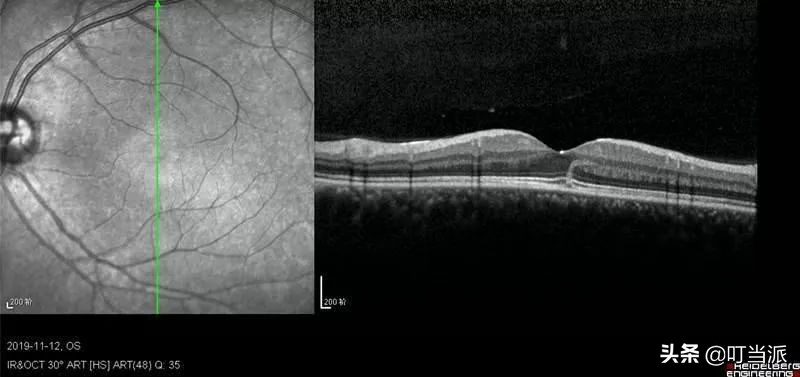

右眼黄斑中心凹全层水肿

江阴市人民医院眼科主任徐学东检查后发现,黄先生双眼黄斑水肿、右眼感光细胞层断裂,并且视力从 1.0 跌到了 0.6。医生给黄先生使用药物促进水肿消退,改善局部微循环并且营养眼部神经。

几天后复查,黄先生的水肿明显消退,视力恢复到了 0.8,但是眼睛看东西还是觉得正中间有黑点。

左眼黄斑中心凹偏颞侧水肿

特别是后极部黄斑区,一旦发生激光损伤,会造成视力下降,眼前黑影。有些严重的损伤会造成视力和眼前黑影永久损害。